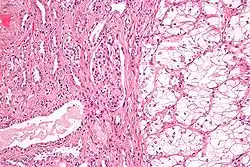

| Micrograph of the most common type of renal cell carcinoma (clear cell)—on right of the image; non-tumour kidney is on the left of the image. Nephrectomy specimen. H&E stain | |